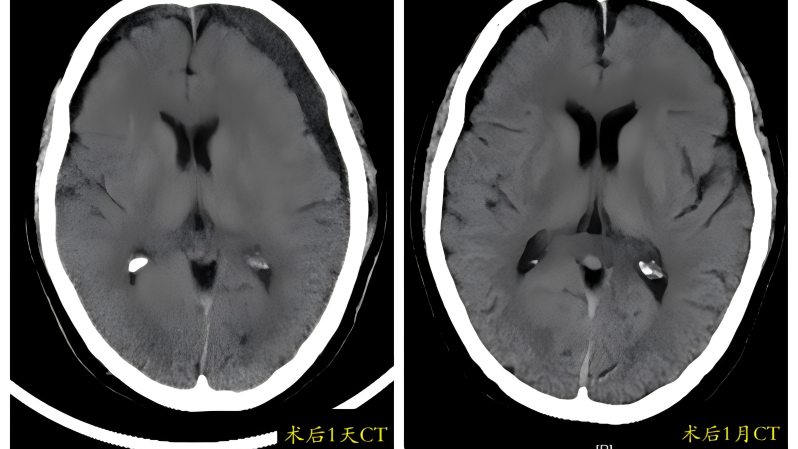

82岁的周奶奶(化名)近期出现神志恍惚、寡言少语、肢体无力、行走困难甚至小便失禁,家人起初误以为是“老年痴呆”。症状加重后送至贵州航天医院,经影像检查确诊为“慢性硬膜下血肿”。颅内较大血肿压迫脑组织,导致了这些神经功能损害。我院神经外科团队采用“微创引流”手术成功清除了血肿。术后1周,周奶奶康复出院;术后1月复查显示,受压脑组织复位良好,血肿无复发。 常见诱因与特点 该病多见于伴有脑萎缩的老年人,轻微头部外伤(如晃动、颠簸)即可撕裂脑表面脆弱的小静脉,造成缓慢出血,在脑萎缩、低颅压等因素影响下,血肿可能逐渐增大。典型症状包括记忆力减退、反应迟钝、嗜睡、肢体乏力等,易被忽视或误诊。 科学应对方案 少量无症状: 可尝试药物治疗,定期复查头部CT监测变化。 血肿增多或症状明显: 需及时就诊,颅骨钻孔微创引流术是首选且成熟的手术方式,能有效清除血肿、解除压迫。 防治复发: 脑膜中动脉栓塞术是预防复发的有效辅助手段。 温馨提示 老人轻微磕碰后若逐渐出现上述症状,应警惕慢性硬膜下血肿,即使受伤后早期颅脑CT未见异常,症状出现也需及时复诊,与高血压脑出血不同,慢性硬膜下血肿若能及早发现并规范治疗(如微创引流),通常预后良好。 注:部分图片来源于网络,如有侵权,请联系删除。 贵州航天医院 神经外科专家简介 廖洪民 神经外科党支部书记、主任,主任医师 临床擅长:从事神经外科临床工作30年,对颅脑损伤、脑肿瘤、脑血管病等具有丰富诊疗经验,擅长救治重症颅脑创伤、脑出血微创治疗、脑肿瘤显微手术治疗、脑立体定向手术等。 中国医师协会神经外科分会专科认证医师、贵州省医学会神经外科分会青年委员、遵义市医学会神经外科分会常务委员、遵义市中西医结合学会脑心同治专业委员会常务委员、中国生命关怀协会脑卒中救治及康复照护专业委员会委员、贵州省脑损伤评价质控中心专家库成员、遵义市脑损伤评价医疗质量控制中心专家。 朱家伟 神经外科副主任医师 临床擅长:从事神经外科工作26年,擅长颅脑损伤救治及脑出血微创手术。 遵义市医学会神经外科分会委员、遵义市中西医结合学会脑心同治专业委员会常务委员。 黄建军 神经外科副主任医师 临床擅长:从事神经外科工作20年,对神经外科常见病、急危重症有丰富诊疗经验,熟练掌握神经外科微创手术。 贵州航天医院 神经外科简介 基本情况 贵州航天医院神经外科于2008年独立建科,是首批国家卫健委能力建设和继续教育神经外科建设中心,贵州省神经外科介入联盟单位。现有专业技术人员17人,其中高级职称4人,中级5人,初级7人。 科室配备STORZ神经内镜系统、德国莱卡手术显微镜,国产西山开颅动力系统、蛇牌双极电凝、Mayfield头架等颅脑手术设备,以及无创和有创颅内压监护仪、正中神经刺激仪、脑循环康复治疗仪、排痰机、下肢康复训练器、气垫床、多参数监护仪等现代化医疗设备,为病区各种急、危、重患者的观察、监护和治疗保驾护航。 专科特色 (一)脑出血微创手术治疗 应用范围:各种病因导致的自发性脑出血(高血压脑出血、脑淀粉样血管病相关脑出血、抗凝药物相关脑出血等)。 技术优势:微创、精准、恢复快。 (二)颅脑病变显微切除术 应用范围:颅内各种占位性病变(脑囊肿、脑肿瘤等)。 技术优势:精确度高、创伤小、恢复快。 (三)颅脑创伤综合救治 应用范围:各种类型的颅脑损伤、创伤性颅内血肿及颅脑创伤并发症、后遗症等。 技术优势:快速精准诊断、个体化手术与监护、早期康复干预,伤者病死率低、并发症少。